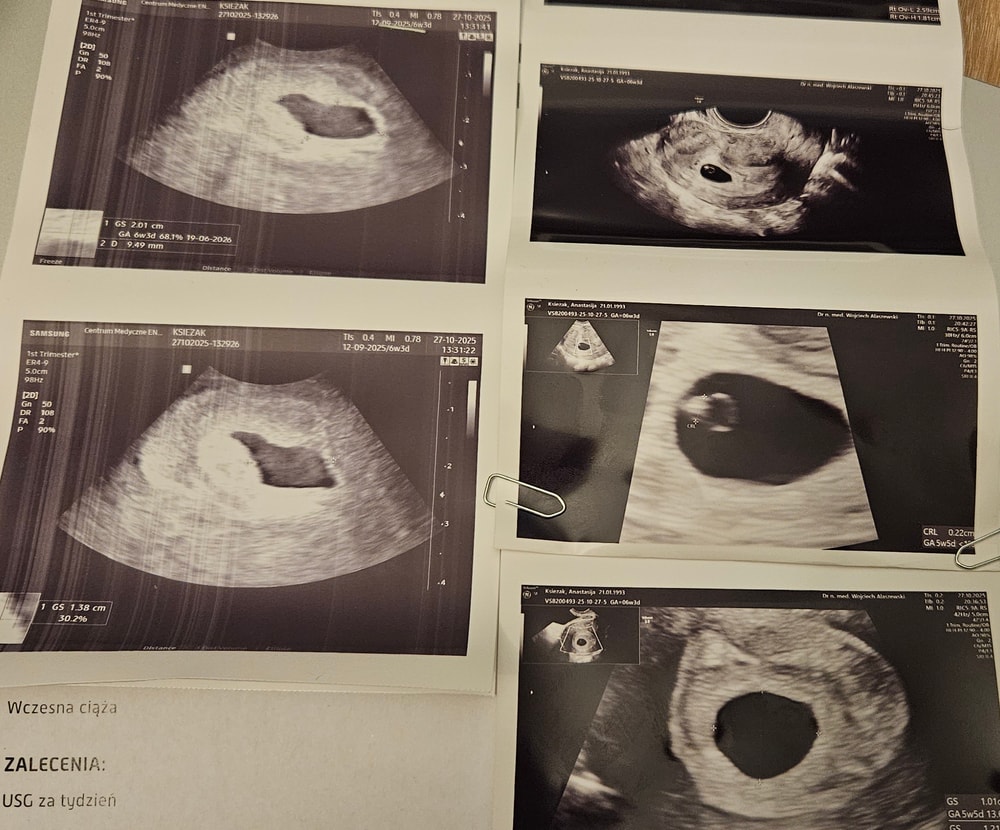

ради интереса, с лево первый узи, с права второй. даже формы ПЯ очень разные эххИзображение

Anastasiya , прекрасно всё видно! Просто совсем ещё крошка малыш. Видимо аппараты разные

Anastasiya , я тоже все вижу, колечко вижу. А колечко это эмбрион и мешочек